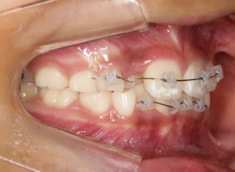

治療法:拡大プレート+フルパッシブブラケット(クリアスナップ)

治療中